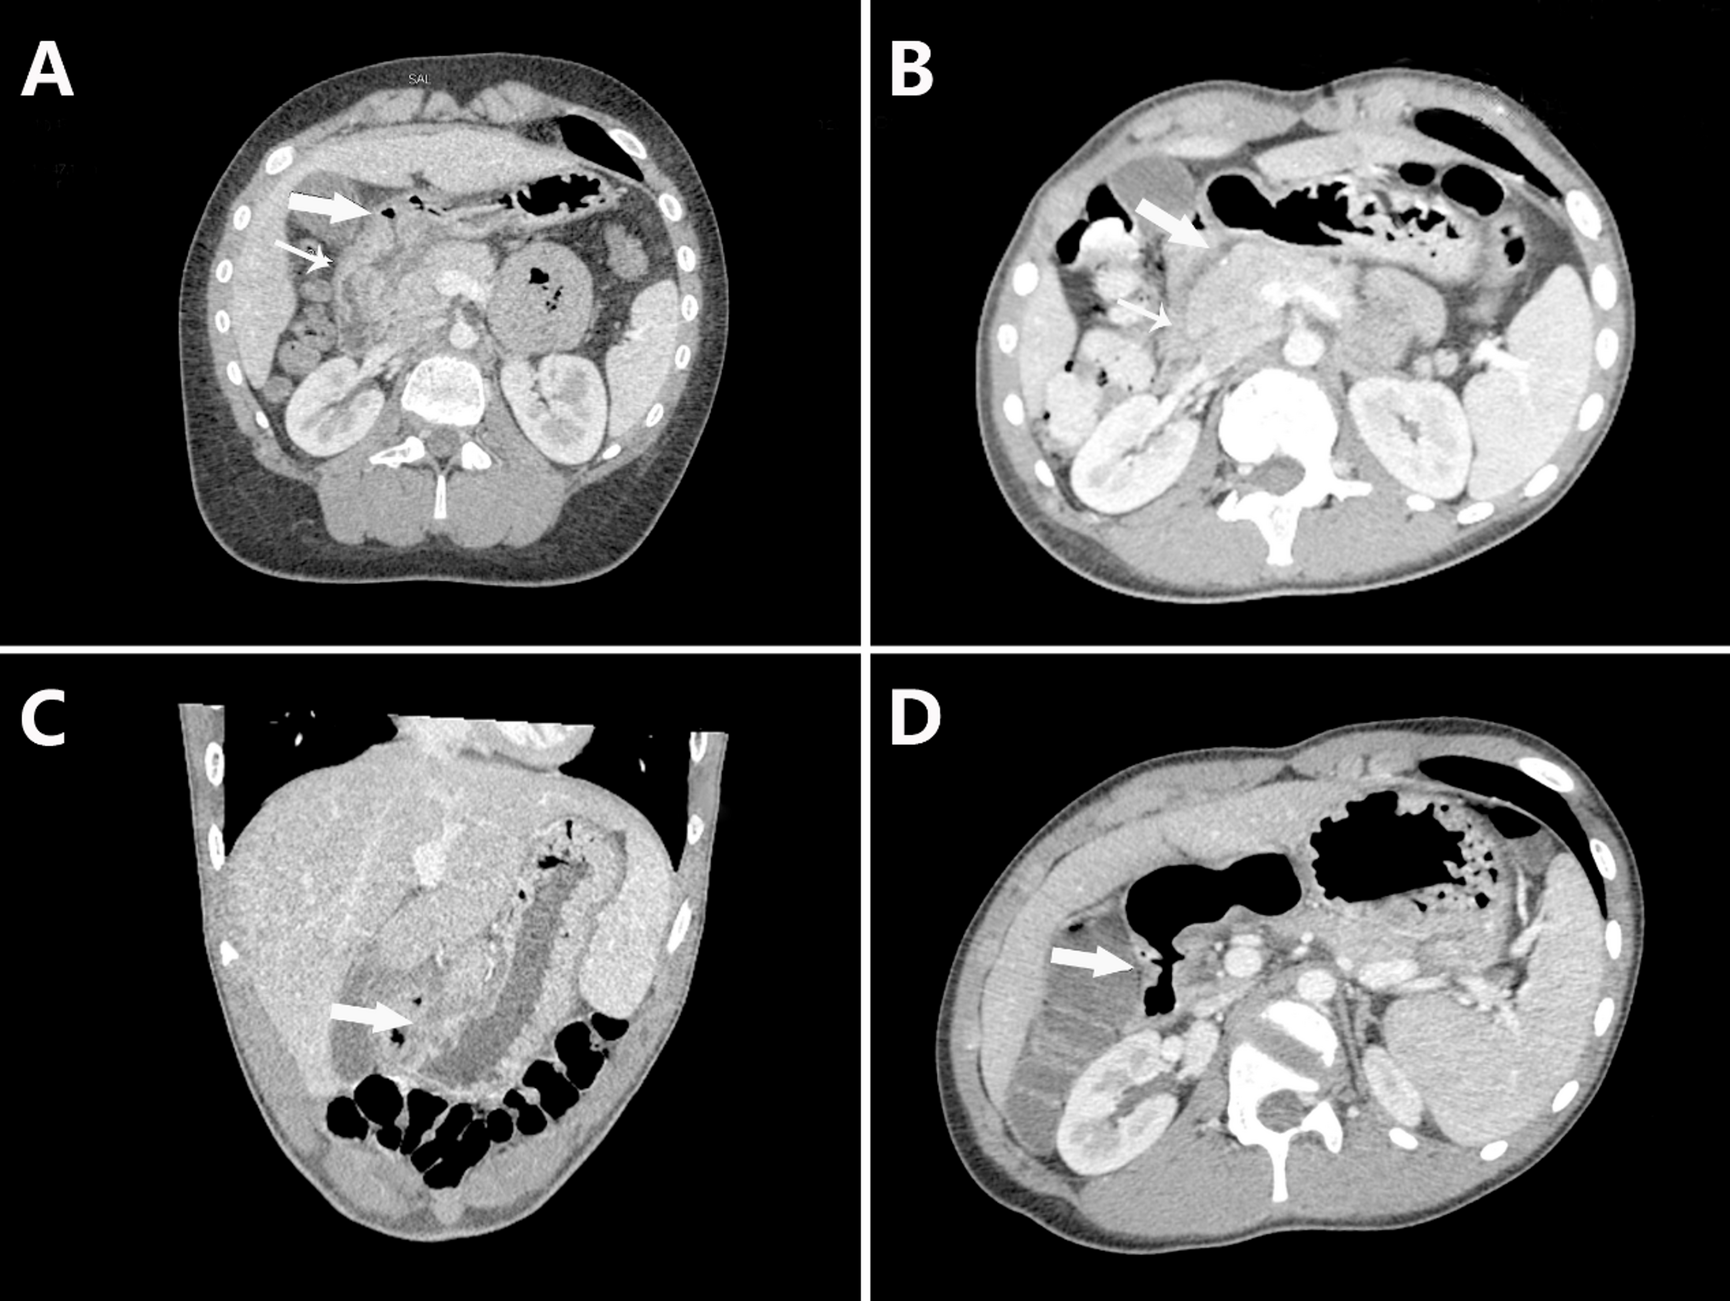

Fig. 3

Abdominal enhanced CT examination of eosinophilic DBU. (A,B) Thickening of the duodenal bulb (large arrow) and descending part (small arrow) in case 10, with improvement after treatment. (C) Thickening of the duodenal bulb (large arrow) in case 3. (D) Thickening of the duodenal bulb (large arrow) in case 18.